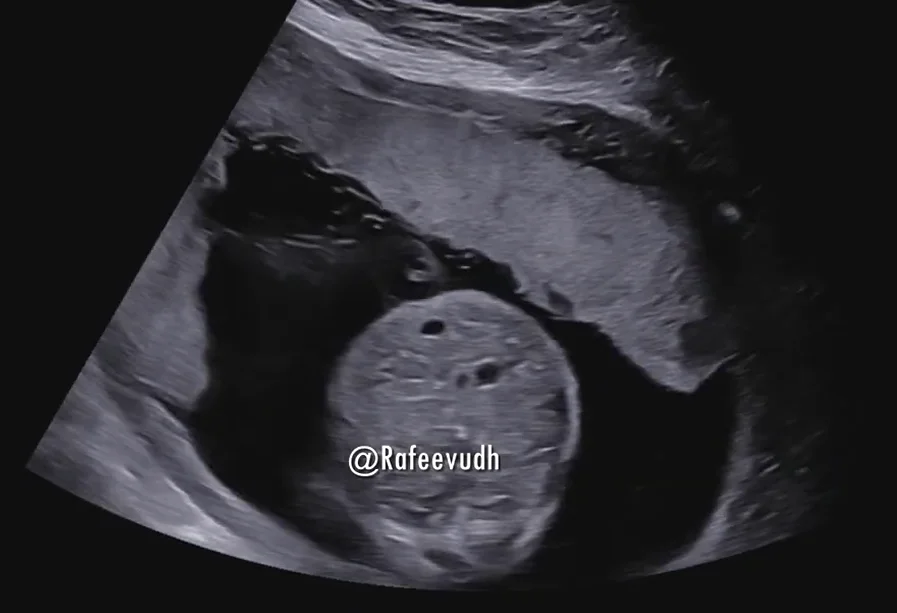

• Thai trứng toàn phần (Complete hydatidiform mole)

• Thai trứng bán phần (Partial hydatidiform mole)